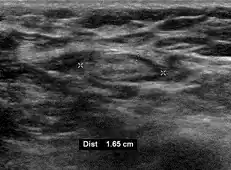

On ultrasound, B-mode imaging depicts lymph node morphology, whilst power Doppler can assess the vascular pattern.[28] B-mode imaging features that can distinguish metastasis and lymphoma include size, shape, calcification, loss of hilar architecture, as well as intranodal necrosis.[28] Soft tissue edema and nodal matting on B-mode imaging suggests tuberculous cervical lymphadenitis or previous radiation therapy.[28] Serial monitoring of nodal size and vascularity are useful in assessing treatment response.[28]

- Absence of the fatty hilum

- Increased focal cortical thickness greater than 3 cm

- Doppler ultrasonography that shows hyperaemic blood flow in the hilum and central cortex and/or abnormal (non-hilar cortical) blood flow.[26]